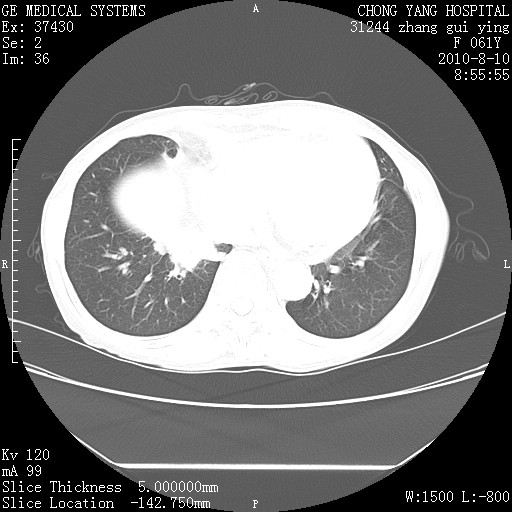

标题: CT28314:F61Y胸部增强,发热咳嗽一周入院,后面的为一周前平 [打印本页]

标题: CT28314:F61Y胸部增强,发热咳嗽一周入院,后面的为一周前平

右肺下叶中心性肺癌可能性大

1、支持考虑右侧中央型肺癌伴右肺中叶节段性不张及下叶支气管黏液痰栓    2、左肺上叶舌段感染。

支持右下肺中央型肺癌并左上肺感染.

支持3楼意见,还要考虑:纵隔及肺门淋巴结转移、右侧少量胸腔积液。

确切的说:1:右肺下叶中心型肺癌侵及中叶支气管并中叶不张,纵膈淋巴结转移。2:左肺舌叶炎症。3:右侧胸腔少量积液

块影平扫32hu,动静脉期62-70hu.

右肺下叶内基底段近膈不规则肿块,考虑右肺下叶周围型肺癌可能性大。